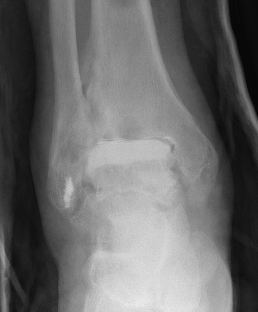

CT

Evaluate bone stock to determine if TAR is appropriate